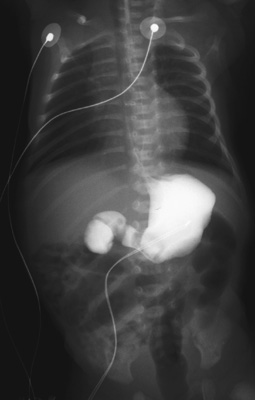

![]() | This upper GI series with bright contrast material in a child reveals a focal area of obstruction in the duodenum. The contrast material outlines the stomach and in the distal duodenum beyond the obstruction. On ultrasound of a fetus in utero, instead of contrast there would be air to produce the characteristic "double bubble" sign of duodenal atresia. |